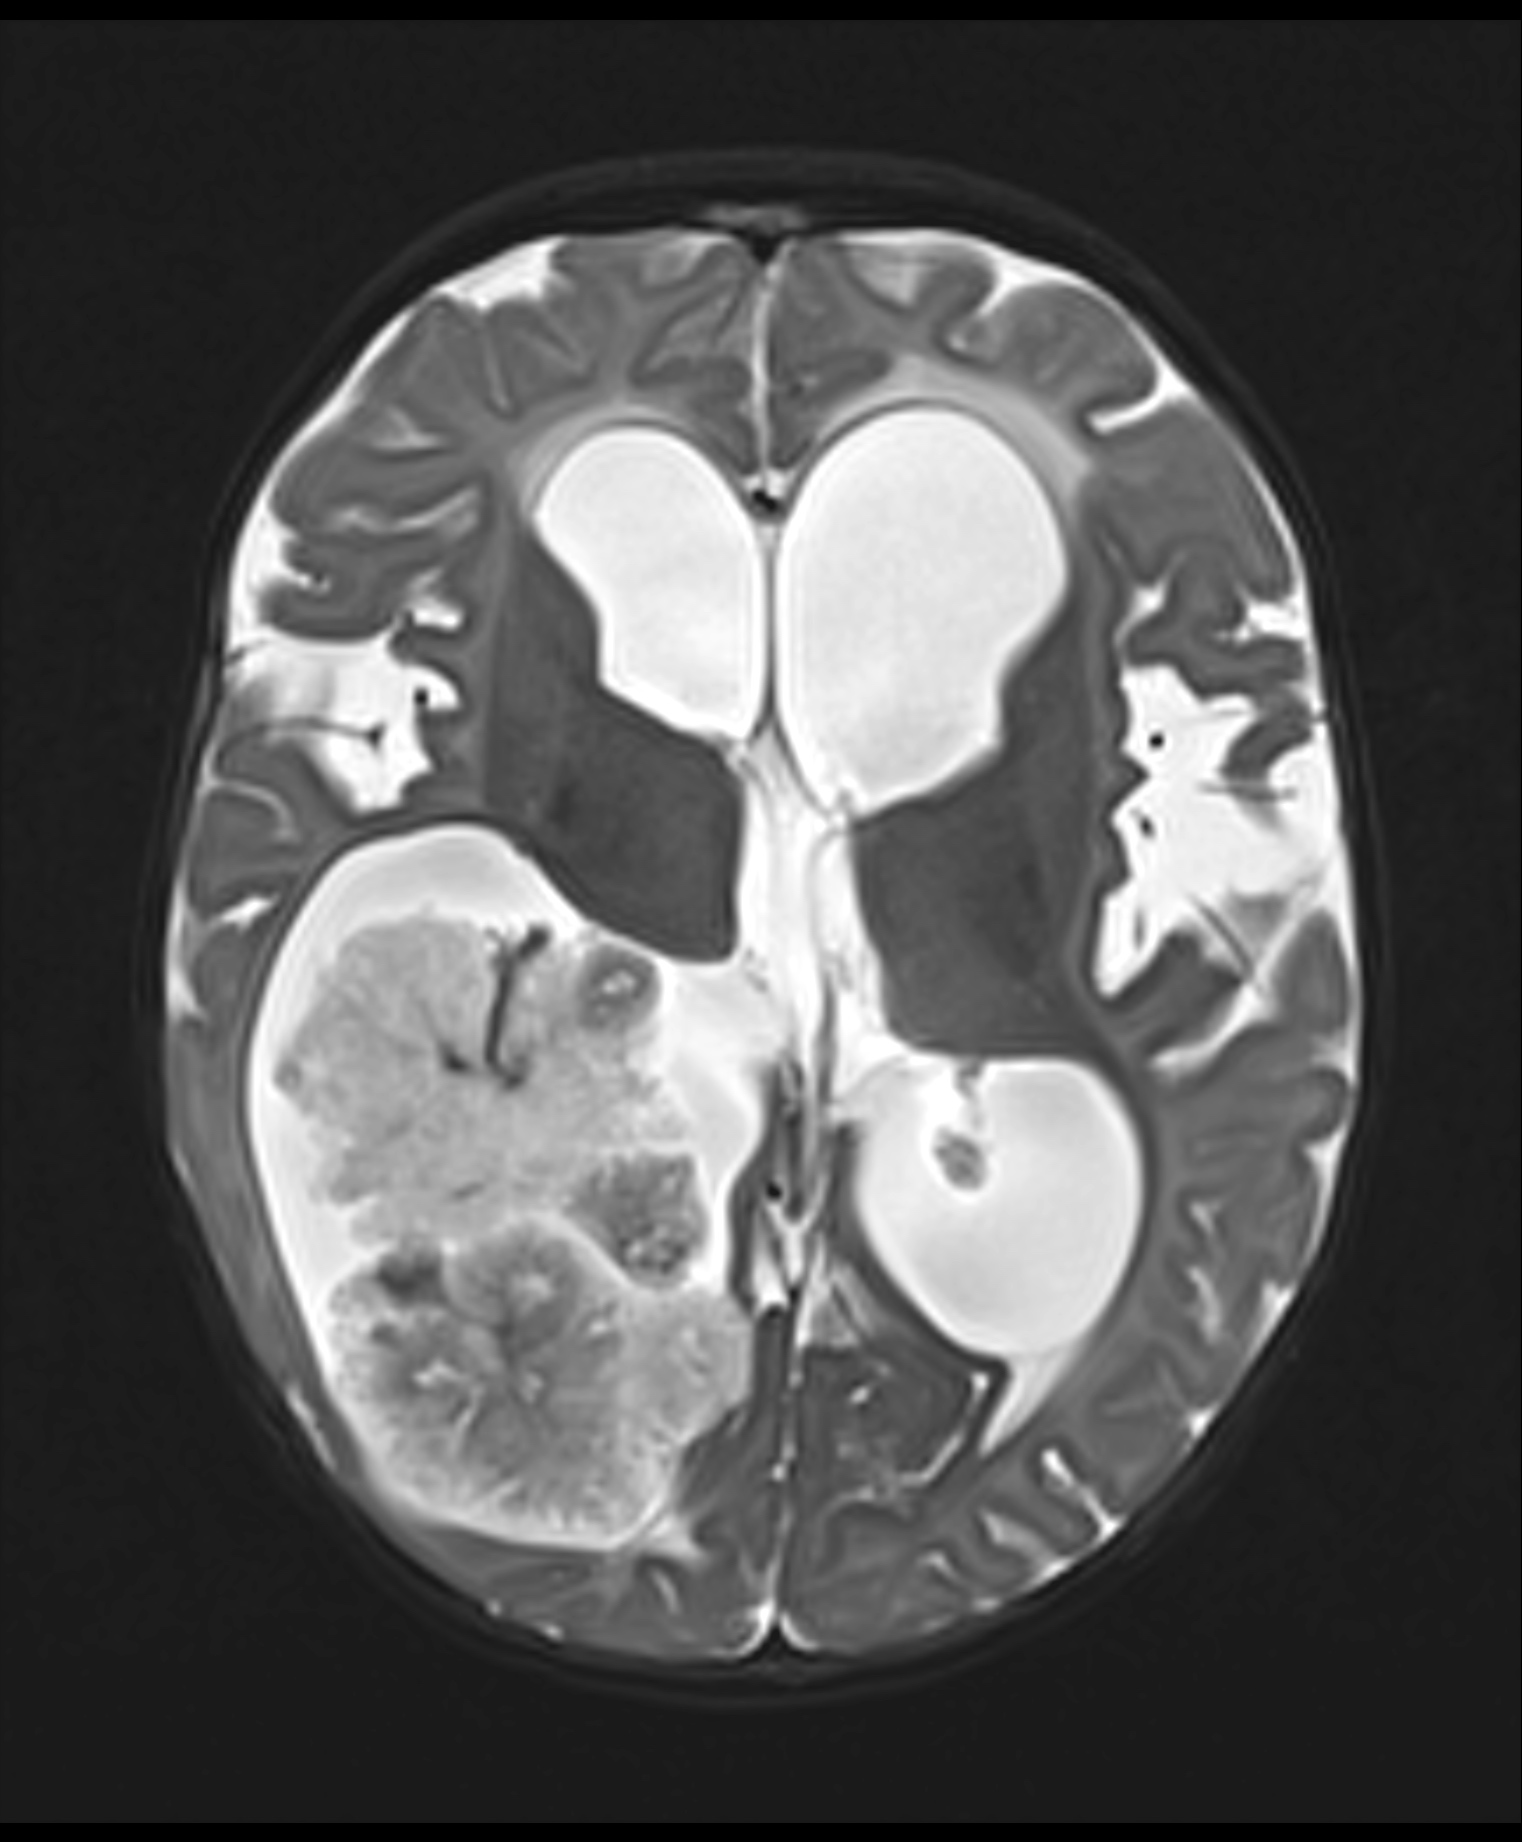

Radiology description

- Intraventricular papillary or lobulated lesions on MRI; hypo or isointense on T1, hyper or isointense on T2 and enhanced in postcontrast imaging (Cancer Imaging 2019;19:17)